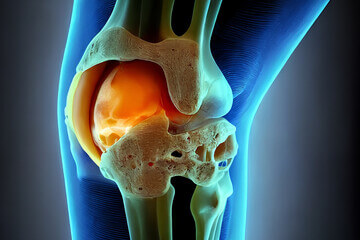

무릎에 물이 무엇인지 설명하자면 관절액입니다. 관절은 연골에 영양을 공급하고 체중을 분산시켜 관절을 보호하는 점성 유체로 채워져 있습니다.

관절액은 관절을 둘러싸고 있는 주머니 안에 있는 활액막이라는 조직에서 분비되며 생산과 흡수를 반복하면서 항상 5cc 정도의 일정한 양을 유지합니다.

그러나 무릎 관절에 염증이나 손상이 발생하면 활막으로부터 무릎을 보호하기 위해 많은 양의 관절액이 분비되며 생성되는 양보다 흡수되는 양이 많습니다. 이 상태는 무릎 활액막염라고도 하며 무릎에 물이 차 있는 상황입니다.

무릎 관절에는 끈적끈적한 관절액이 분비되어 부드럽게 움직일 수 있습니다. 이 관절액은 활막에서 분비되며 관절을 적셔 마찰을 방지하고 뼈의 마모나 손상을 방지합니다.

그런데 활막에 염증이 생기거나 외부 충격이 가해지면 활액이 과도하게 분비가 되는데 활액이 너무 많이 분비되면 제대로 흡수되지 못할 때 고여서 무릎에 물이 찬 것을 말합니다. 그러니까 관절액이 과도하게 생성되는 상태를 의미하며 활액막염이라고 합니다.